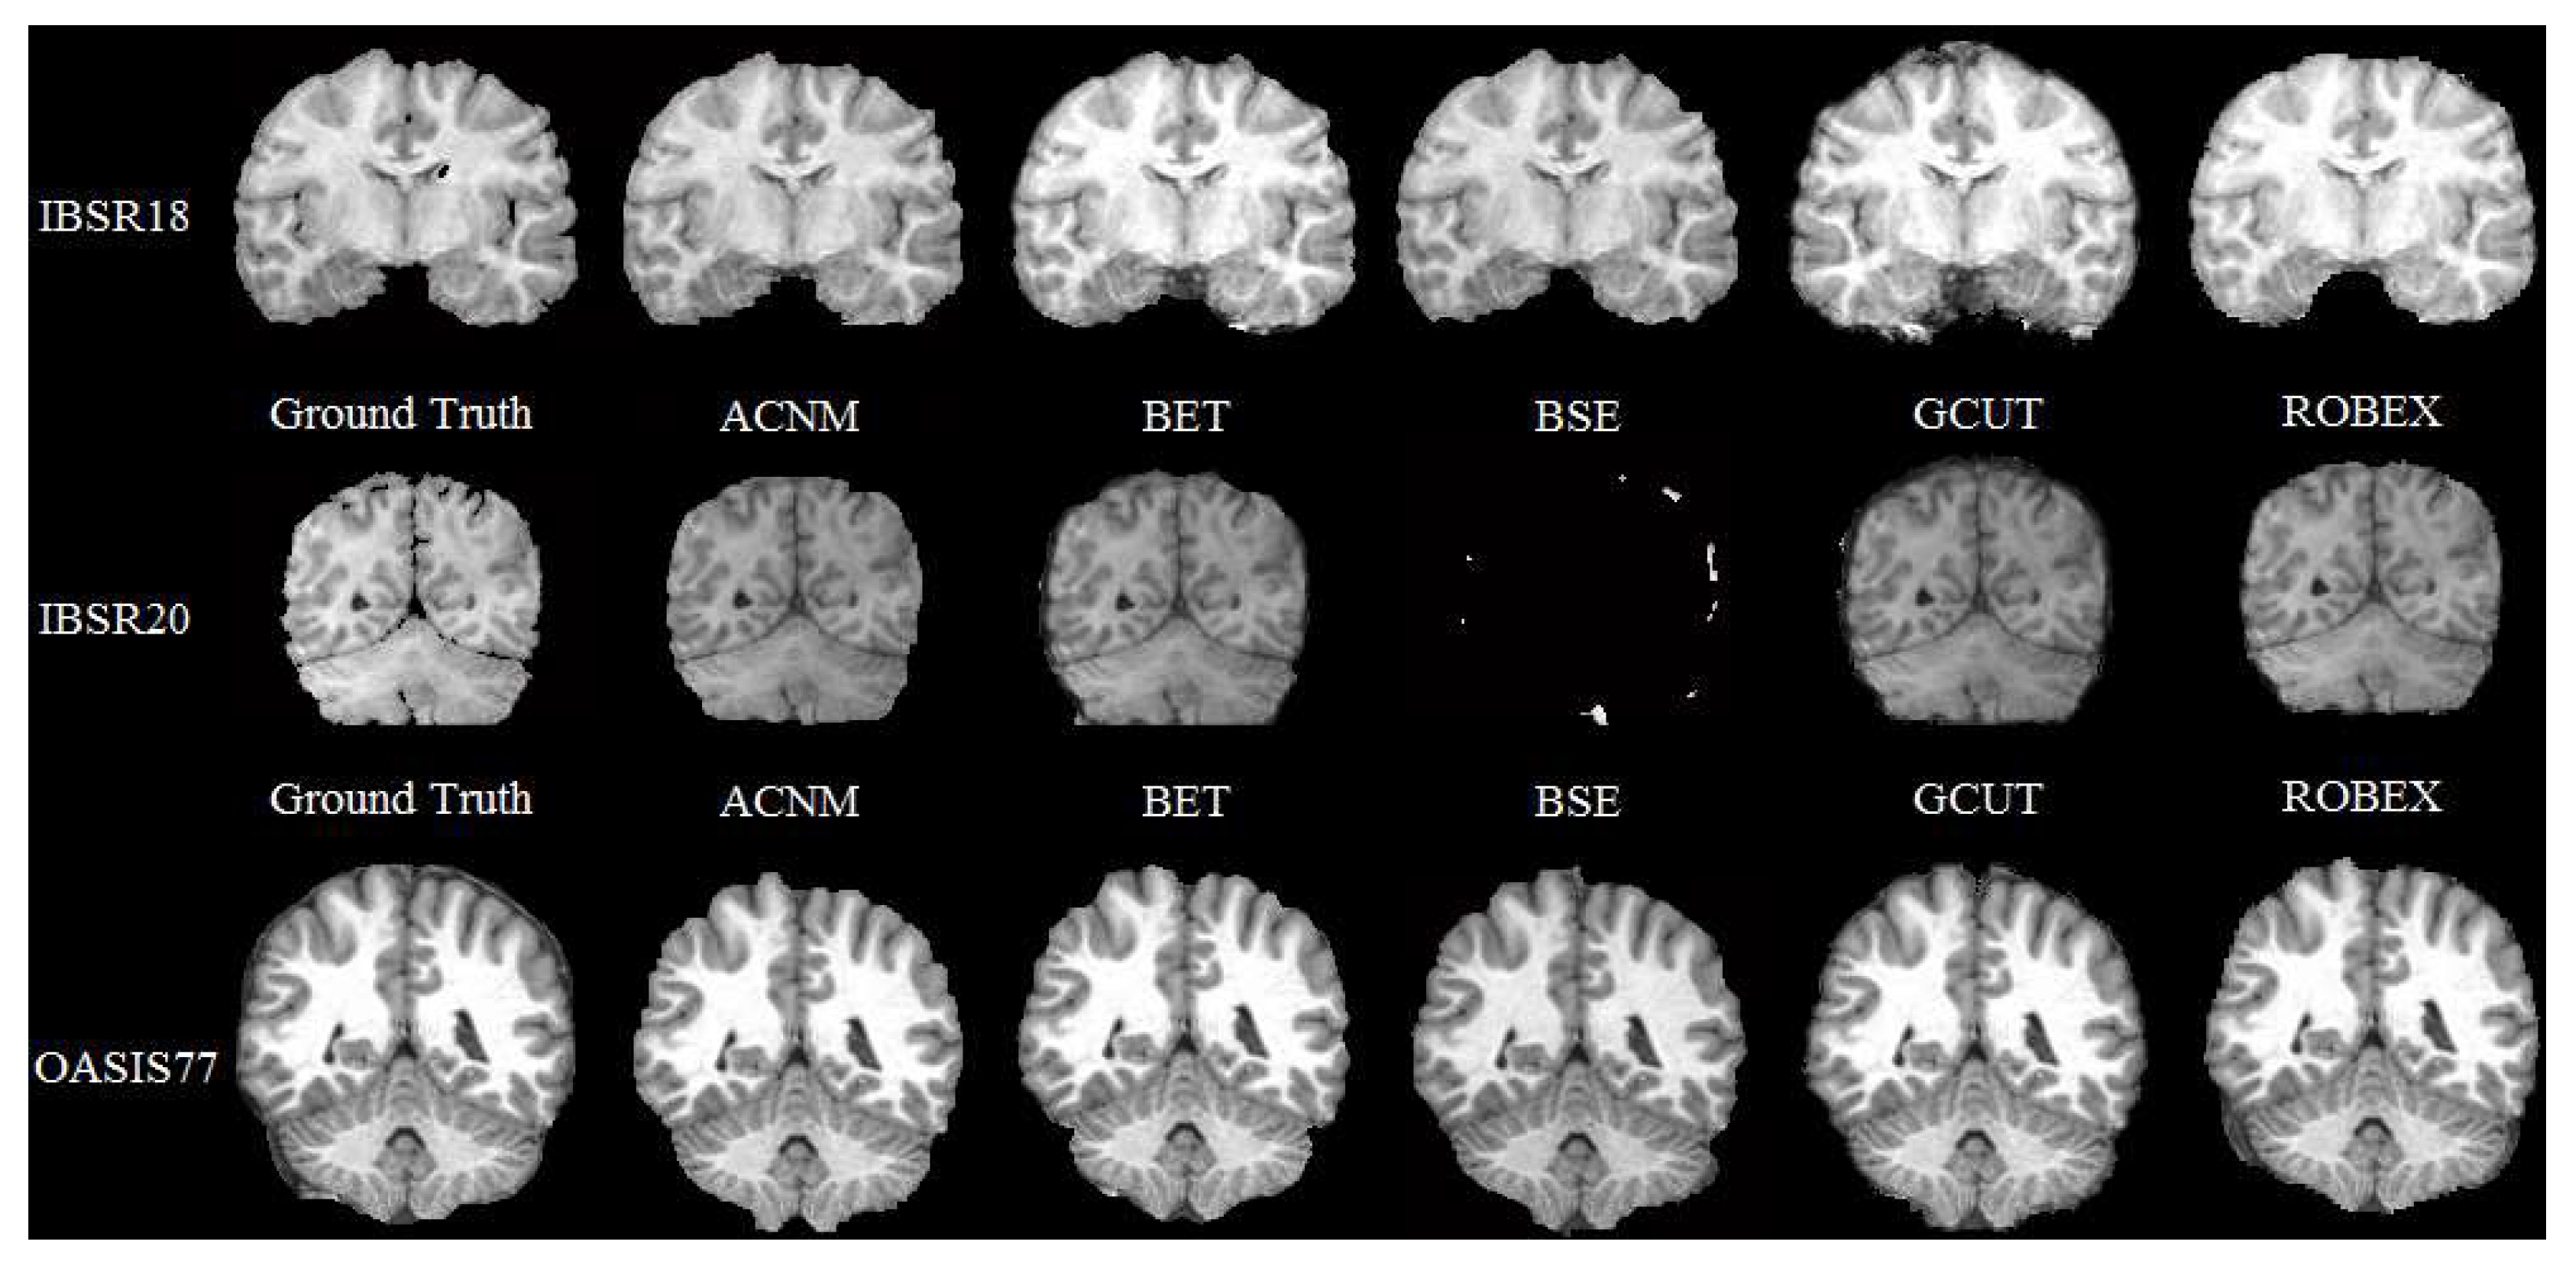

4. Discussion